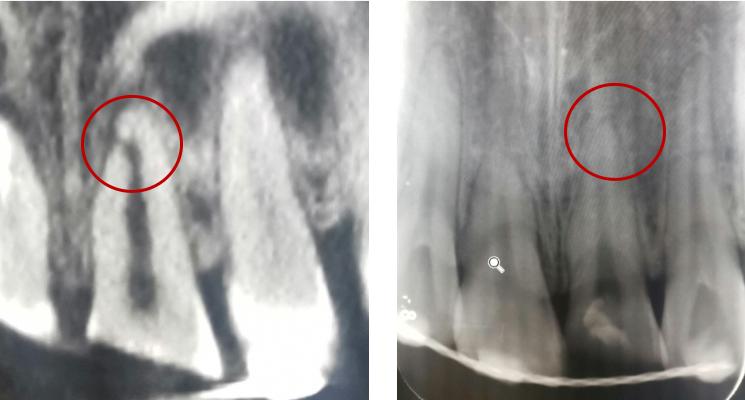

根折--根颈1/3

治疗方案:复位松动移位的牙冠,夹板固定4周,折断线近牙颈部固定时间延至4个月,定期检测折断线愈合情况,监测牙髓状态。牙髓坏死或感染则进行冠方的牙髓治疗。如颈部折断后断片异常松动,治疗则同冠根折。

根折--根中1/3

治疗方案:复位松动移位的牙冠,夹板固定4周,定期检测折断线愈合情况,监测牙髓状态。牙髓坏死或感染则进行冠方的牙髓治疗。